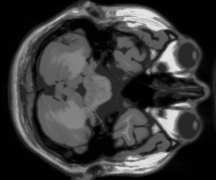

IV-C MRI dataset

In this subsection, an MRI dataset of size is chosen to test our model. Except for the 30 bands used for the test, we select another 10 bands from the raw data as the dictionary training set. And different from the color image experiments, the dictionary used in this part is of size for working well in most situations.

Color images own three channels only, while MRI data often include dozen or hundred bands. In this way, the relationship among different bands will be closer, which is very advantageous to the TNN-based method. However, our SNN-based model still shows its superiority after introducing the CSC prior. The same as color images, we randomly pick 10%, 20%, and 30% samples as the observations, and the results are shown in Fig. 6. It’s intuitive that LRTC-CSC models achieve the best performance among these models, while HaLRTC achieves the worst performance, which verified the effectiveness of CSC regularization. In particular, LRTC-CSC models work well on detailed recovery comparing to TNN-3DTV and Framelet-TV. When the missing rate reaches 90%, our model can still hold a relatively clear result.

Fig. 8 further shows the recovery performance in every band. Both the PSNR and SSIM values of each band show the superiority of LRTC-CSC models. Note that TNN-3DTV can achieve a high SSIM value approaching LRTC-CSC. However, there is a gap between them on the edge band of the whole MRI data. The proposed model LRTC-CSC-I achieves a performance promotion of and with respect to PSNR and SSIM over the results of TNN-3DTV. Moreover, the performances of LRTC-TNN and LRTC-CSC-II on edge band are similar to TNN-3DTV, which implies the shortcoming of TNN-based methods. In other words, TNN can not handle the edge information due to lacking enough neighbors, which is determined by its predominant characteristic of global information capturing. The peformance of TT rank-based method is not satisfactory in MRI data recovering experiments because of imposing KA on the unbalanced tensor [48][49].